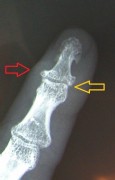

Finger-end joint stiffening and middle joint replacement in rheumatoid patients.

Left: Red Arrow: Horn-like deposits as an sign of osteoarthritis, yellow arrow: complete destruction of the joints, with inflammation and pain at rest and at work.